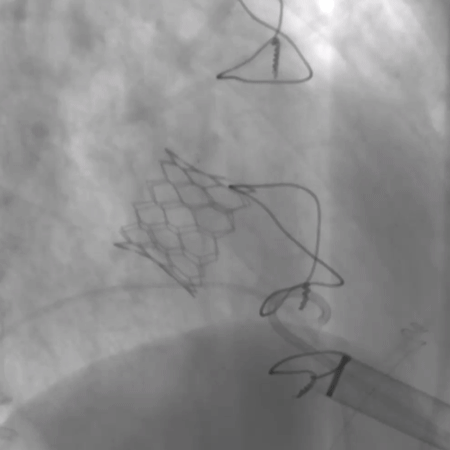

瓣中瓣植入后无反流及瓣周漏

术前经详尽评估患者病情,通过CT重建测量瓣环直径、左室流出道面积。结合之前外科换瓣手术入路,决定采用经心尖途径行二尖瓣“瓣中瓣”手术。术中选用27# Renato®球扩式瓣中瓣,顺利通过心尖途径植入。手术过程顺利,几乎无出血。最终瓣中瓣植入位置理想,功能表现出色,左室造影及经食道超声观察无明显瓣中及瓣周反流。二尖瓣峰值流速由术前2.5m/s降至1.6m/s,平均跨瓣压差由11mmHg降至5mmHg。